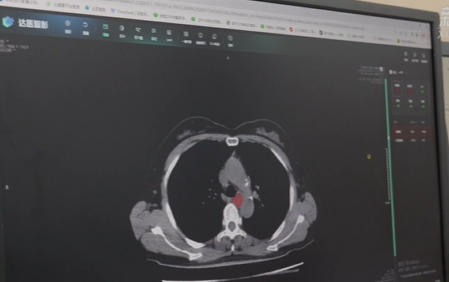

近年来,甘肃兰州加快推进卫生健康行业“人工智能+”应用的创新发展,部分医院“AI医生”上岗服务患者,打造智慧医疗“新场景”。